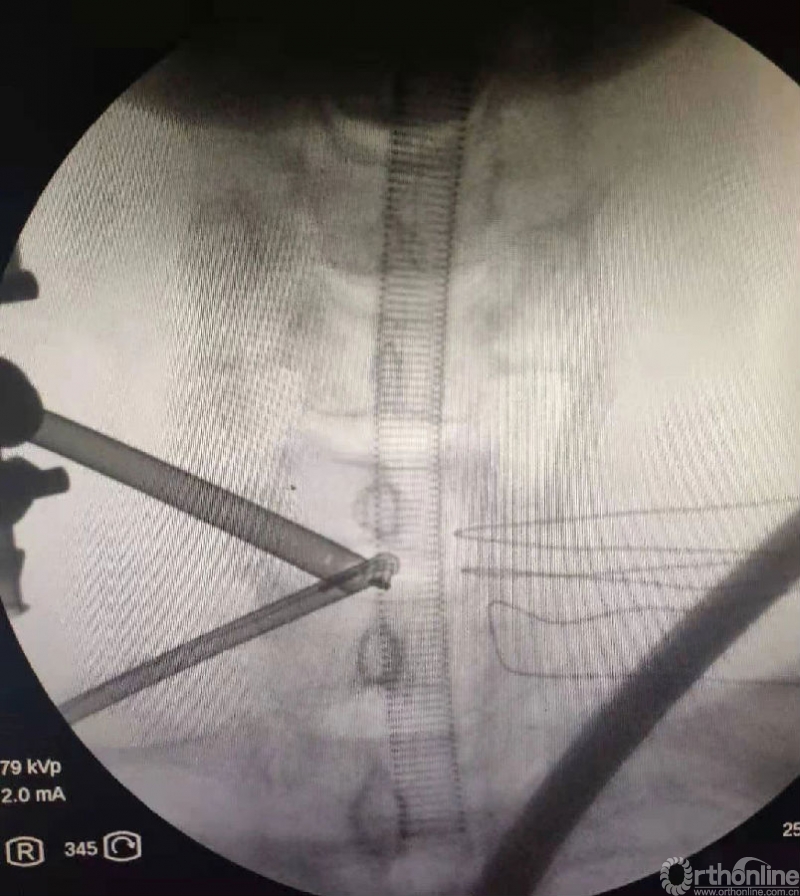

以腰椎为例

脊柱外科医生常常在术后进行减压程度的评估,以期望神经根的充分减压,而不是侧隐窝的减压不彻底。

工欲善其事,必先利其器。减压时应用的镜子有0度和30度之分。

30度镜子有更广的视野,但是在减压的时候,在没有充分对corner部位减压的情况下,可能通过旋转30度镜子即可清楚的看到神经根及椎弓根内壁。

但这也可能误导临床医生掌握一个错误的减压外界,进而过早的结束手术。

0度镜子则不存在这种情况。其手术视野与开放手术视野一样,不存在视野的偏差,corner部位对神经根的遮挡可全部看到并在其监视下完成减压。

当我们用30度镜子看到减压范围足够的时候,使用0度镜子观察可能减压范围并不足够。这并不是说30度的镜子不能做到充分减压,可能需要掌握一定技巧和经验以便用30度镜子完成充分减压。

我们可以确保30度的镜子对向尾端或头端以评估减压的范围,这样中线及关节突关节方位的视野不会出现视野偏差,也就是确保冷光源接口与横突中线平面平行。

当然不是说不能用30度镜子,在使用时大家一定要有一个视野偏差的概念。我们建议手术时应准备两种镜子,一般使用0度镜子减压,当存在视野狭小时更换30度镜子。0度镜子使用时确实存在不舒服或视野小及遮挡情况,也要不断适应和熟练掌握。